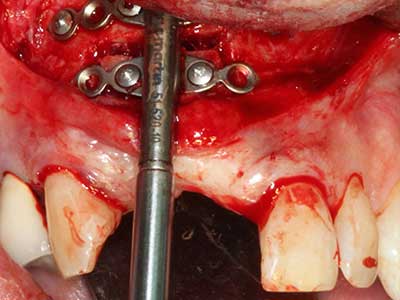

Bei der Knochenblockentnahme zeigen sich weitere Vorteile für die Piezochirurgie: Neben der bereits beschriebenen hohen Präzision bei der Osteotomie stellt sich gerade die Verwendung der dünnen Sägespitzen als besonders materialschonend heraus. Bei der Verwendung insbesondere von Lindemannfräsen sind mit deutlich höheren Entnahmeverlusten durch die dickere Instrumentenspitze zu rechnen (Lakshmiganthan, Gokulanathan et al. 2012). Die insbesondere bei retromolar entnommenen Blocktransplantaten notwendige basale Abtrennung wird durch speziell hierfür vorgesehene rechtwinklige Sägen erleichtert, so dass die Piezochirurgie als präzises, übersichtliches und sicheres Verfahren zur retromolaren Knochenblockgewinnung angesehen wird (Happe 2007) (Abb. 1-12).

Indikation: Bone Splitting